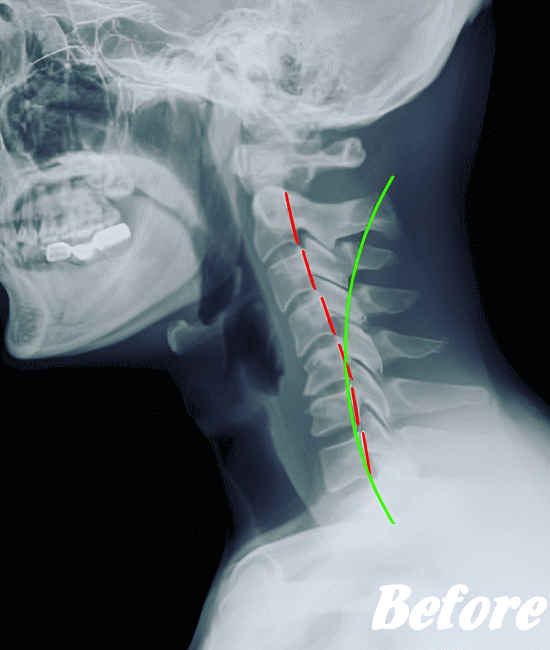

ストレートネックも、首に負担がかかりやすいので、注意が必要です。

HALOカイロプラクティック☆平和島整体院では、首の筋肉をゆるめていくため、まずは骨盤(特に仙腸関節)を調整、背骨(腰椎、胸椎、頚椎)を調整、そして肩甲胸郭を調整します。

そして、肩甲胸郭、つまり肩甲骨の動きをよくし、肋骨を広げ、丸まった背をのばし、胸が大きく広がるように調整します。肩甲骨には首の筋肉がつながっているので、調整は必須です。

状態に応じて、頭蓋骨を調整し、身体をリラックスさせます。基本的に、頚性神経筋症候群は姿勢の悪さに起因するところが大きいので、深く呼吸できる身体に改善していくことで、首のコリは取れていきます。